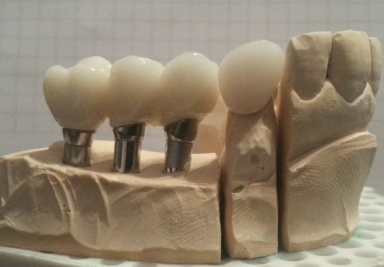

Zirconium crowns on teeth and implants

Crowns on teeth and implants

Dental implants, porcelain crowns

dental implants, porcelain and zirconium crowns